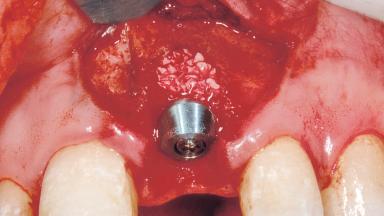

Bone Augmentation Horizontal|Simultaneous

Augmentation Materials Xenogenous|Membrane

Soft Tissue Grafting Simultaneous

Placement Protocol Immediate implant placement